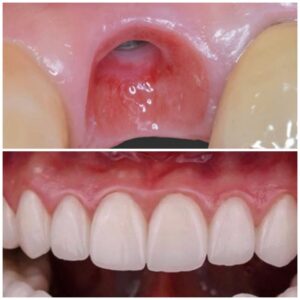

جماليات زراعة الأسنان

يتم تخطيط وتنفيذ إجراء زراعة الأسنان بعناية لضمان أن ترميم الأسنان يبدو طبيعيًا في الشكل واللون والمكان. نعطي الأولوية لراحة مرضانا بالإضافة إلى الجماليات. وهذا يتطلب مزيجًا مثاليًا من العبقرية الفنية والجراحية. لذلك ، يتم تنفيذ جميع حالات الزرع لدينا من قبل فريق من أطباء الأسنان التجميليين وأخصائي زراعة الأسنان.